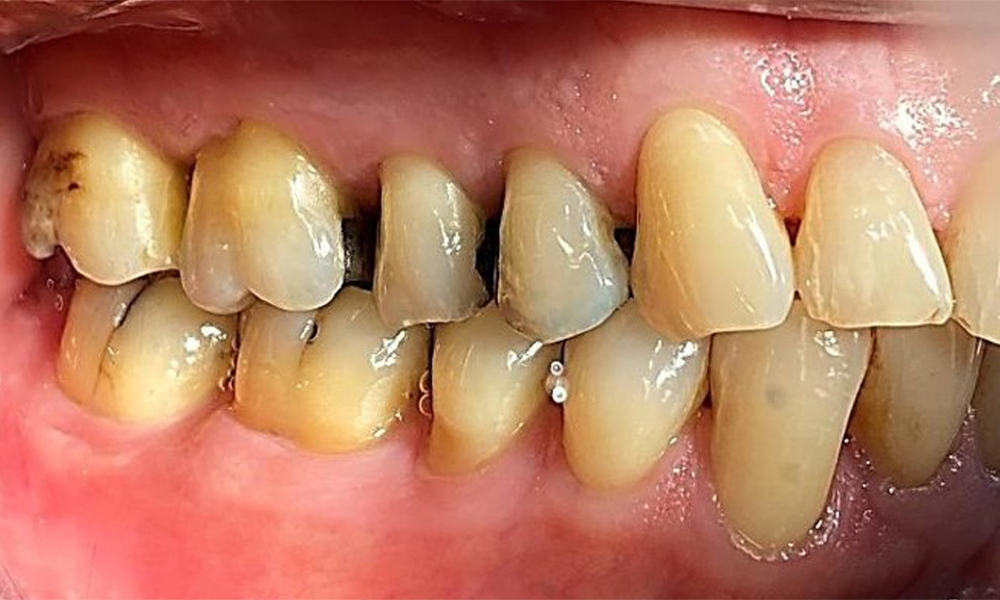

Left lateral view including the recessions.

Fig. 4 Left lateral view including the recessions. © Dr R. Krapf

The patient has a full dentition with 28 teeth, which includes amalgam and composite fillings in the molar and premolar regions. There is a visible clinical marginal gap present on tooth 14. Tooth 27 has an adequate gold inlay. There are also generalized attritions and abrasions. (Fig. 2, Fig. 3, Fig. 4, Fig. 5, Fig. 6)

Periodontal findings

The patient has stage II, grade B periodontitis (5). At 1 to 3 mm, the clinical probing depths were within the physiological range. Localized probing depths of 5 mm were observed on the mesiopalatal aspects on both 17 and 27. There are generalized recessions of 1–3 mm with partial loss of the interdental papillae (Fig. 2, Fig. 3, Fig. 4)